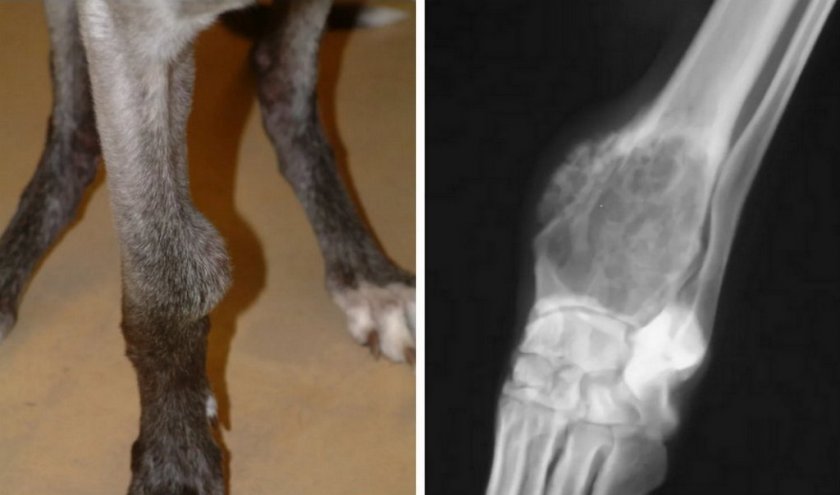

Костная (остеогенная)

Из всех видов новообразований опорно-двигательного аппарата собак почти 90% приходится на остеосаркомы.

Данный вид патологии опасен тем, что начинает развиваться очень глубоко в кости животного, при этом быстро разрастается и поражает всю кость изнутри, после чего мутировавшие частицы опухоли отбрасываются от основного очага в другие части скелета, а также внутренние органы.

Например, подозрению на остеосаркому у собаки должны вызвать такие симптомы:

- видимое увеличение размеров кости;

- хромота, припадание на одну лапу;

- частые переломы, даже без серьёзных травм.

Частой причиной хромоты у собаки является вывих, ушиб или другое травматическое повреждение конечности, о котором хозяин может и не знать. Однако при механическом воздействии на лапу проблемы с двигательной функцией обычно возникают сразу и потом, по мере затухания болевого синдрома, состояние животного постепенно нормализуется. Остеосаркома ведёт себя по-другому: сначала хромота проявляется незначительно и, что характерно, лишь время от времени, но затем промежутки хорошего самочувствия становятся всё короче, пока в конце концов двигательная функция не оказывается полностью нарушенной.